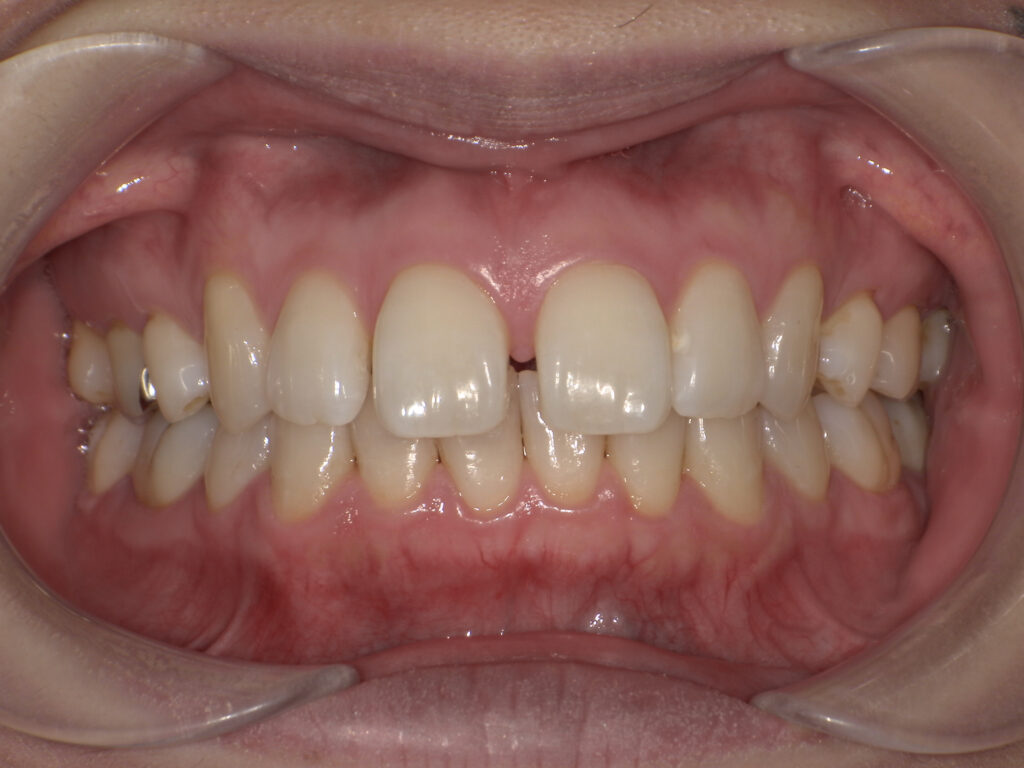

【ワイヤー矯正】

矯正前(正面・側貌)

矯正後(正面・側貌)

主訴出っ歯、すきっ歯

初診年齢15歳

治療内容、装置頬側ブラケットを用いた永久歯全体の矯正治療、アンカースクリュー

抜歯の有無抜歯有

(左右下顎第二小臼歯、左右上顎第一小臼歯抜歯)

治療期間20ヶ月

費用総額1,097,800円(税込)

(相談料、検査料、診断料、動的治療費、抜歯費、アンカースクリュー埋入、除去費、保定期間料等含む)

治療のリスク、副作用歯の移動に伴う痛み

上下顎前歯部の歯根吸収

装置による口内炎

ブラッシング不良によるむし歯、歯周炎